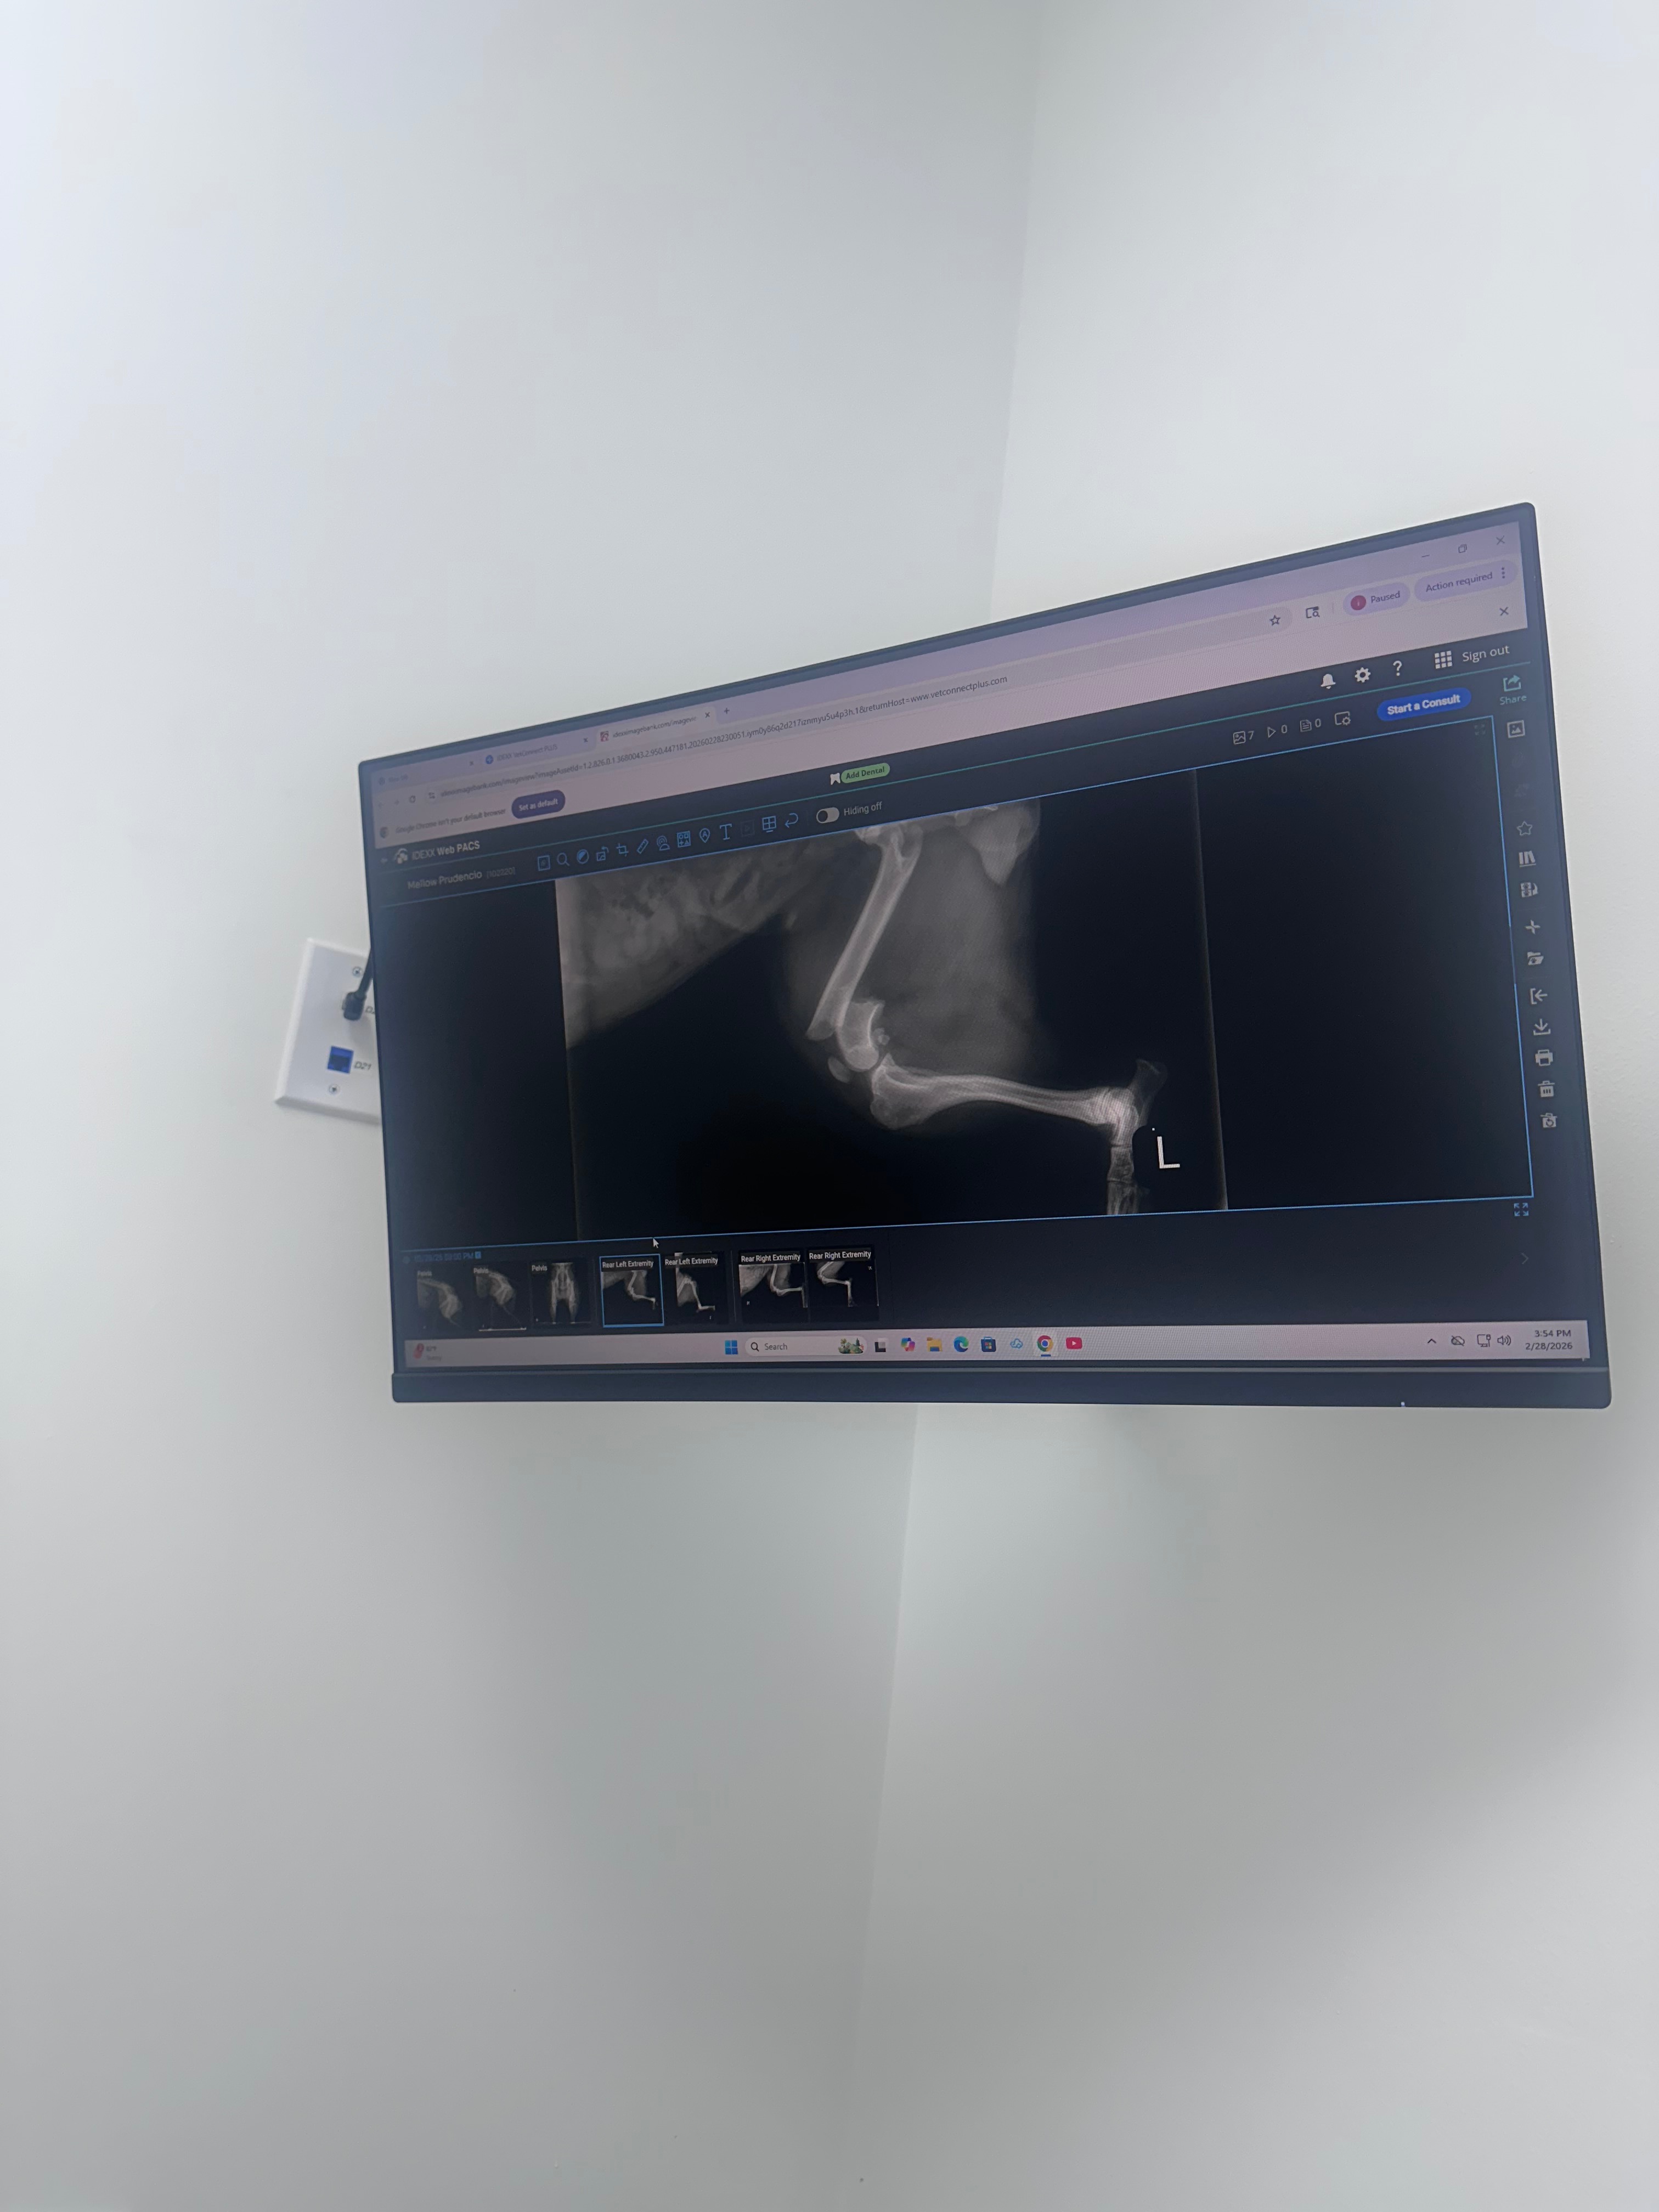

hello! my dog jumped out of our window in our apartment and has fractured her femur. this is definitely unfortunate events with rent around the corner. my roommate and i are trying to gather up money for the surgery, our first fur baby in years and we are asking for any help/advice/shares.